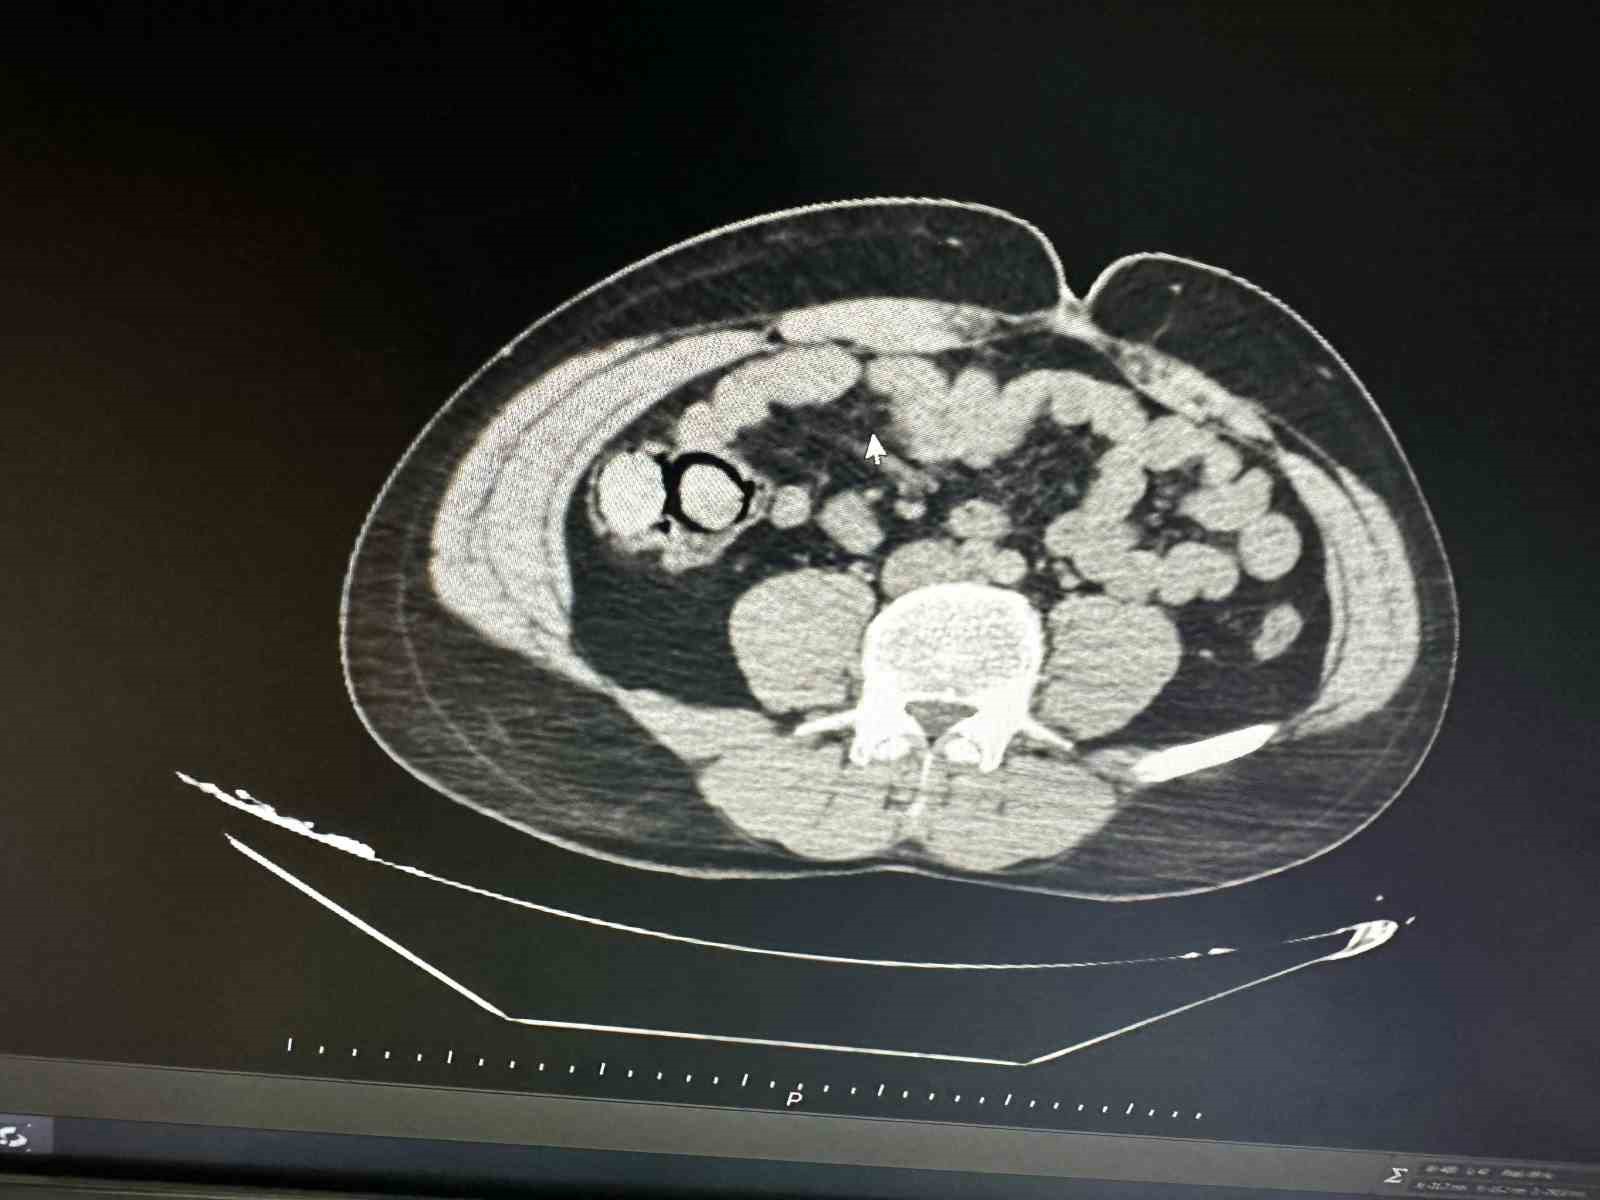

Son Dakika: Antalya Büyükşehir Belediye Başkanı Muhittin Böcek Hastaneye Kaldırıldı